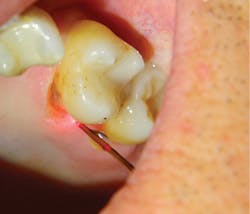

Lastly, it is very important to consider a laser’s water absorption. By providing plenty of water on the tooth surface, we can safely remove hard tooth structure with great visibility and precision. The flip side is that by reducing water supplied at the soft-tissue surface, we are able to sculpt gingival tissue while maintaining coagulation without deep thermal penetration—the laser penetrates only 2.3 microns in soft tissues. This results in a clear surgical field and also enables us to perform subgingival Class V restorations and gingival recontouring in the same appointment, with minimal postoperative discomfort. Restoring difficult clinical scenarios, such as external resorption (figures 6a–6d) is no longer a problem.

Figures 6a–6d: Gingival recontouring and restoration of Class V external resorption lesion in the same appointment